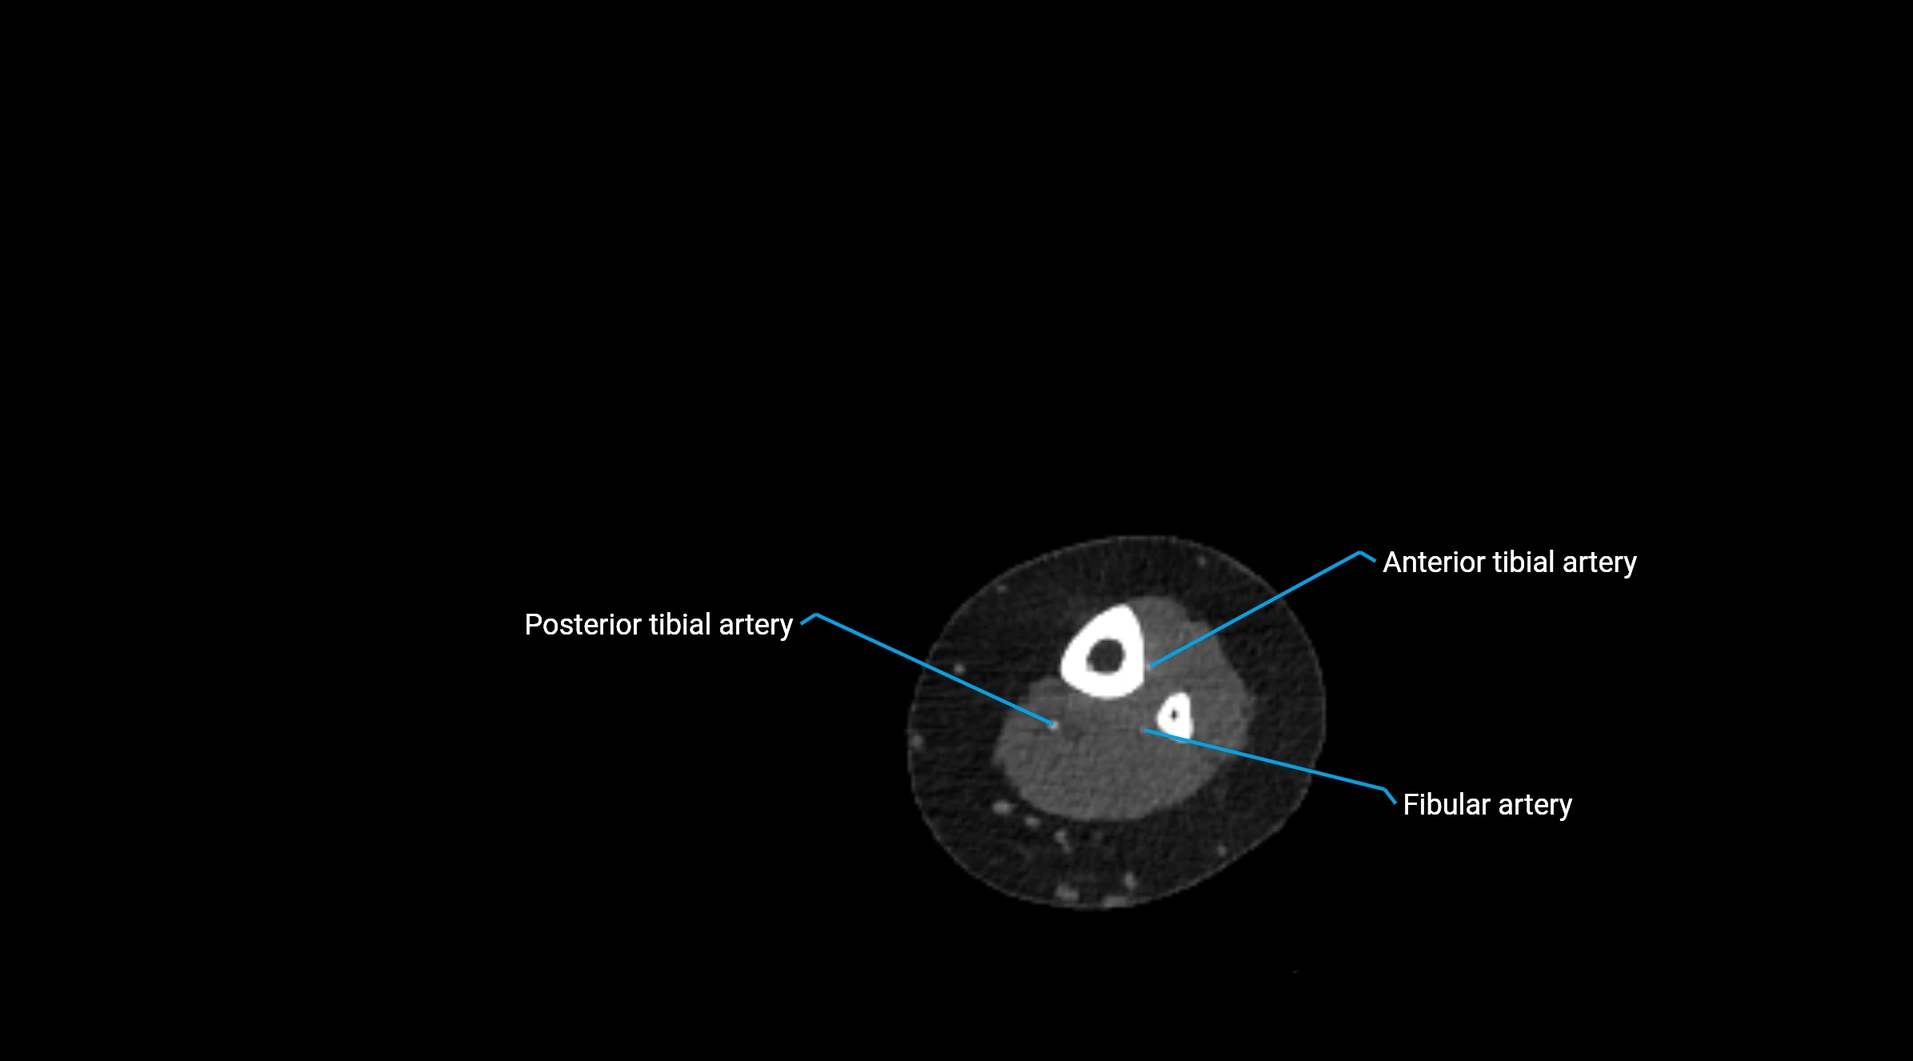

Contrast-enhanced CT (CTA):

• Gold standard for abdominal aortic imaging

• Provides excellent detail of lumen, wall, aneurysm, thrombus, and branch vessels

• Multiplanar and 3D reconstructions help in aneurysm measurement, stent graft planning, and dissection evaluation